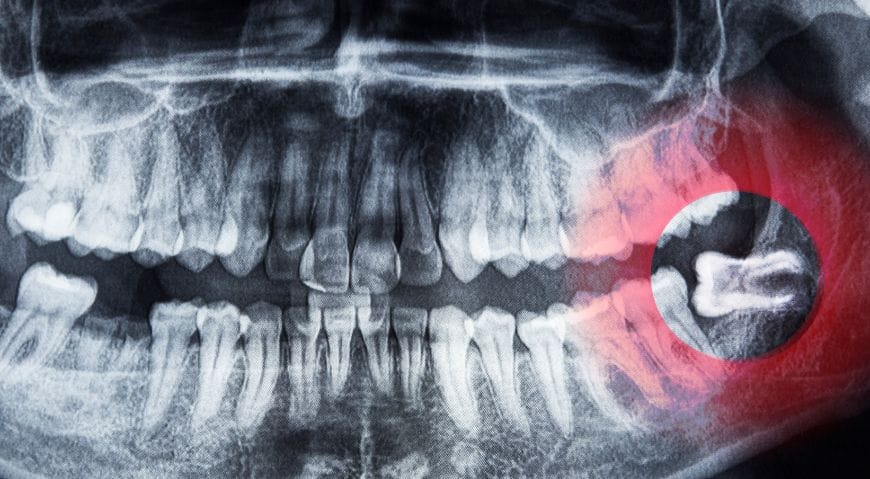

Por eso, es fundamental realizar revisiones periódicas y radiografías panorámicas para evaluar su posición y prevenir problemas futuros.

Se realiza una radiografía panorámica para analizar la posición de la muela y planificar la intervención. - Anestesia local